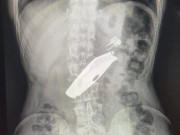

Нож и зажигалку проглотил сельчанин на севере Казахстана

Нож и зажигалку проглотил сельчанин на севере Казахстана (27.04.2020, 17:28)

Мужчина, проглотивший зажигалку и складной нож, попал под нож хирурга в СКО. Делать операцию и доставать предметы пришлось в экстренном порядке, пишет NUR.KZ. Предметы вытащили из брюшной полос...